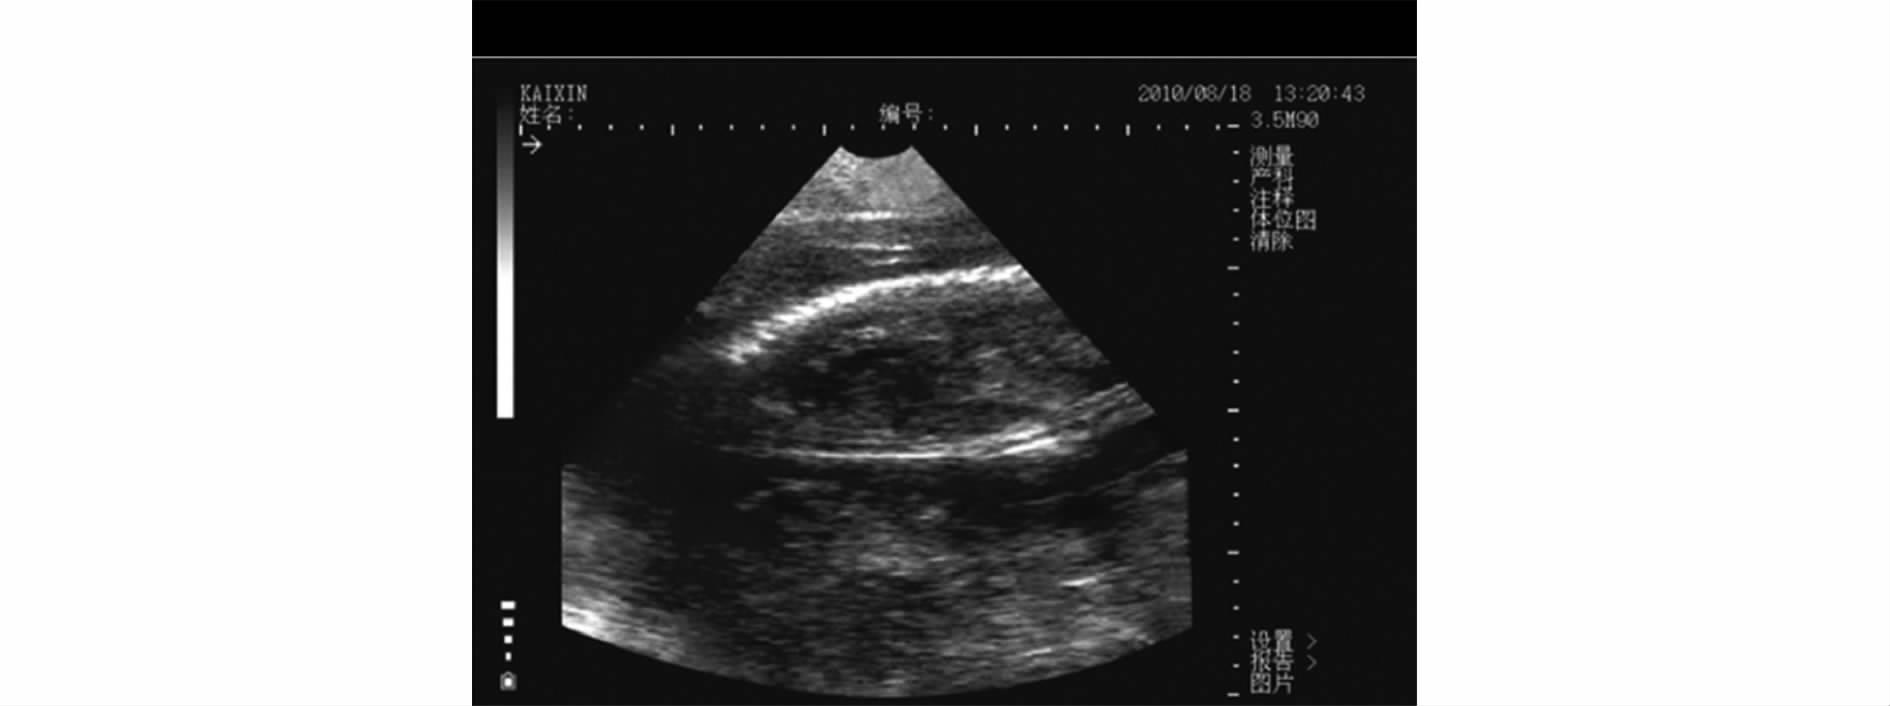

妊娠中后期在下腹部可以大范围探到胎儿,胎位各式各样,有向上、向下、平行、重叠等。妊娠85d胎儿脊柱清晰显示(见图13);95d胎儿脊柱、胸骨及体

腔分辨清晰[4]。

图13 母猪妊娠86d图像